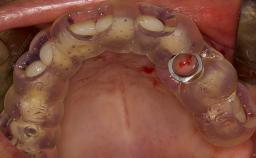

- list the indications for the lateral SFE technique

- describe the surgical treatment concept and steps for the lateral SFE technique and assess the prognosis of this procedure

- discuss the grafting materials used in lateral SFE and the indications for use of membranes